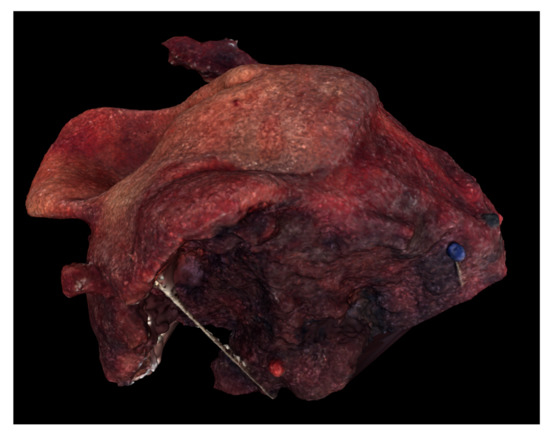

Digital 3D model of Case 2 using Meshlab.

Figure 6.

Digital 3D model of Case 3 using Meshlab.